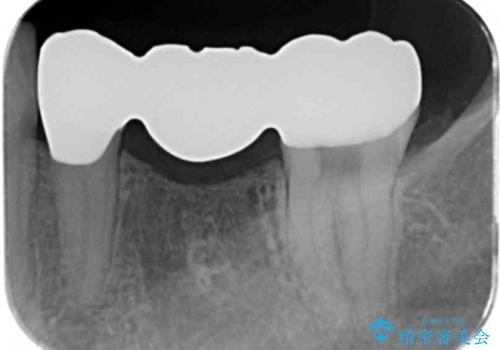

- 左下の銀歯の状態が悪く抜歯してブリッジにした患者様です。

途中全体矯正をはさみ、根の向きが並行になった状態でブリッジを入れることができました。